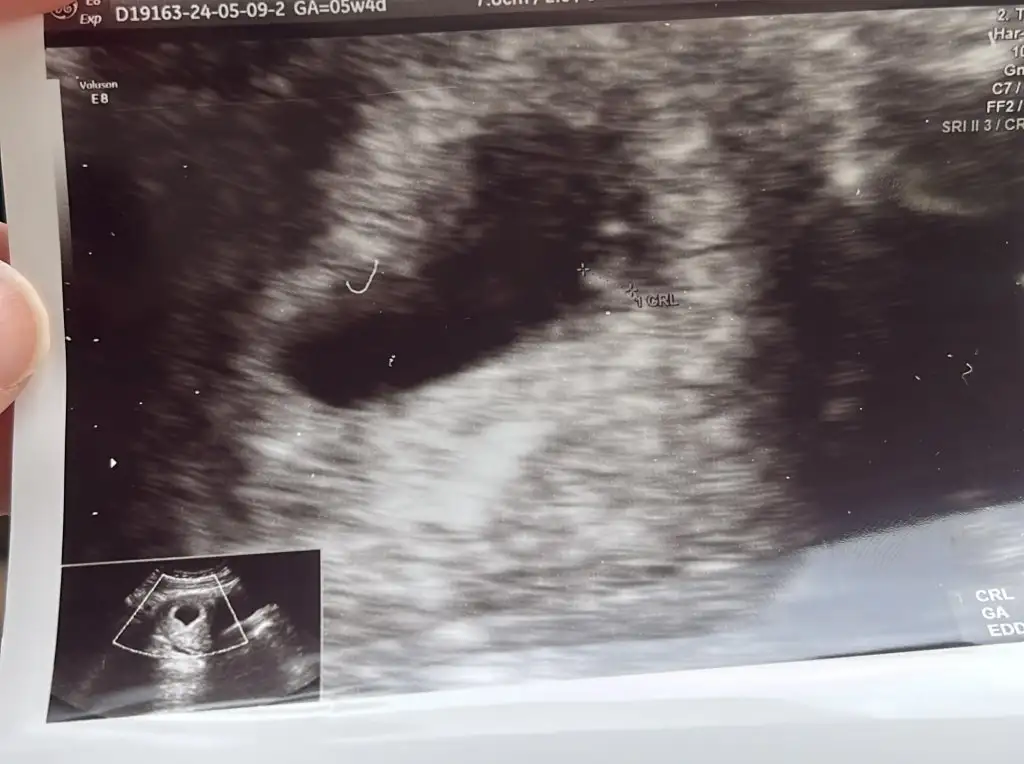

Seninki de kalp şeklinde çıkmış yuvarlak olmadığı için erkek diyeceğimKızlar benim de 5+6 bugğn keseyi görmeye diye gittim kalp atışını kısacık duyduk cinsiyet için yorum yapabilir misiniz

Eki Görüntüle 3425278 Eki Görüntüle 3425279